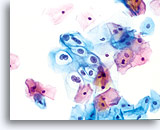

The ThinPrep Pap Test® minimizes the troublesome artifacts inherent in smear and spray fixation. This allows for

the nucleus to be adequately visualized facilitating a more definitive diagnosis. The epithelial cells that are generally incorporated in the ASC category are the mature squamous and squamous metaplastic cells exhibiting changes that are minimal and fall short of a diagnosis of LSIL or HSIL. The nuclei are slightly enlarged and this enlargement is compared to the normal entity of the same cell type. The nuclei may show slight nuclear membrane irregularities but are more often smooth. When dealing with the metaplastic component, one needs to make sure that the irregularities aren’t due to a vacuole(s) pushing the nucleus into the aberrant shape. The chromatin pattern is finely granular and evenly distributed. Chromocenters or nucleoli are generally inconspicuous or absent unless a reactive process is occurring in conjunction with the atypia at which point the differential diagnosis of reactive needs to be considered depending upon the presence or lack of the other criteria.

With either conventional or ThinPrep® slides, an ASC interpretation may arise from any of several different cellular changes, including but not limited to, squamous atypia, atypical squamous metaplasia, and atypical parakeratosis. The criteria for ASC on the ThinPrep Pap Test are as follows:

The images that follow are ThinPrep® Pap Test specimens that reasonably could be interpreted as reactive changes,

ASC-US, and LSIL.